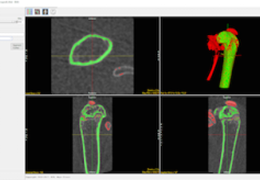

Cortical Bone Segmentation

Once the image data is loaded the BMA add-on will conduct a preliminary segmentation which will allow the module to identify the cortical shell, cortical pores and trabecular tissue regions.

Trabecular Bone Segmentation

Upon user approval the add-on will now complete the segmentation process by identifying the trabecular bone in the trabecular region. Two new regions, the trabecular bone and intra-trabecular space will be derived.